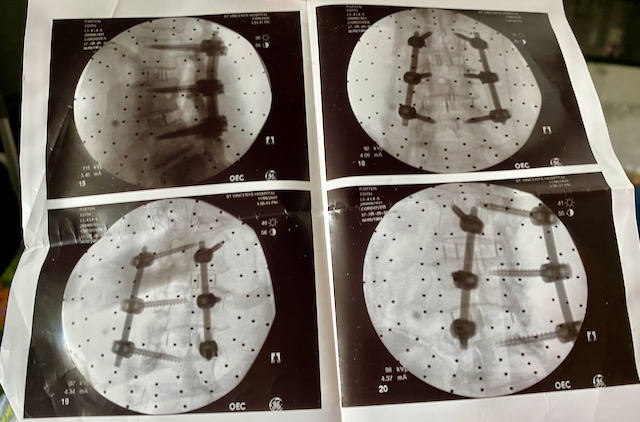

The morning of the surgery I arrived with my husband for my 6:00 a.m. surgery. We didn’t wait in the waiting room very long before getting called back from prep. I remember getting prepped for surgery and getting an IV in my arm and that’s about all I remember before waking up in a room in St. Vincent’s hospital. I’m told that during surgery Dr. Cordover had to find screws small enough for my back. Glad they are small, but they look huge on x-rays.

Dr. Cordover explained that a relatively new robotic back surgery eXtreme Lateral Interbody Fusion (XLIF) would allow for less invasive surgery, one to two-night hospital stay and a quicker recovery time; although, full recovery would still take anywhere from six months to one year. Dr. Cordover said that the XLIF surgery allows for a side incision instead of cutting directly into the back, which could sever and damage nerves. He recommended fusion surgery on two levels of my lumbar. Thank God for new technology.